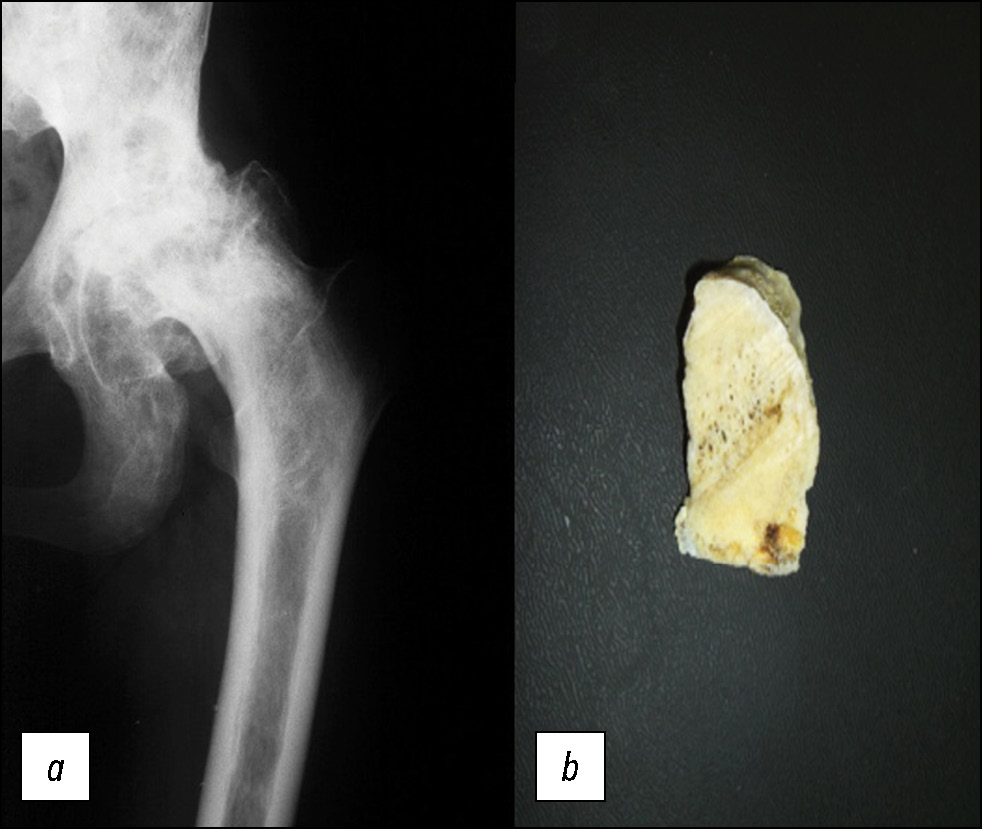

Остеосклероз губчатой кости проксимального метафиза бедра (шейка и межвертельная зона) был выявлен в 63% случаев АНГБК (рис. 6). И только в 15% случаев остеосклероз проксимального метафиза, сопряжённый с АНГБК, сочетался с расширением/вздутием костномозговой полости проксимального отдела диафиза бедра. Увеличение размеров расширения/вздутия в проксимальном отделе диафиза бедренной кости у пациентов после начала патогенетического лечения не наблюдали, в отличие от АНГБК.

Рис. 6. Рентгенограмма тазобедренного сустава в прямой проекции (a), фотография поперечного опила шейки бедра (b). Резко выраженный коксартроз в исходе кортикомедуллярного остеонекроза головки левой бедренной кости с частичным её разрушением. Участки медуллярного остеонекроза с остеосклерозом в проксимальном метафизе.

Fig. 6. X-ray of the hip in direct projection (a), photograph of the transverse sawdust of the femoral neck (b). Pronounced hip osteoarthritis in the outcome of corticomedullary osteonecrosis of the head of the left femur with partial destruction. Areas of medullary osteonecrosis with osteosclerosis in the proximal metaphysis.

Длительная ишемия костной ткани проксимального метаэпифиза бедра при АНГБК подтверждается выявлением распространённых участков остеосклероза при рентгенографии и МРТ-исследовании. Остеосклероз трабекулярной кости виден невооружённым глазом при оперативных вмешательствах, затрудняя, например, имплантацию бедренного компонента эндопротеза.